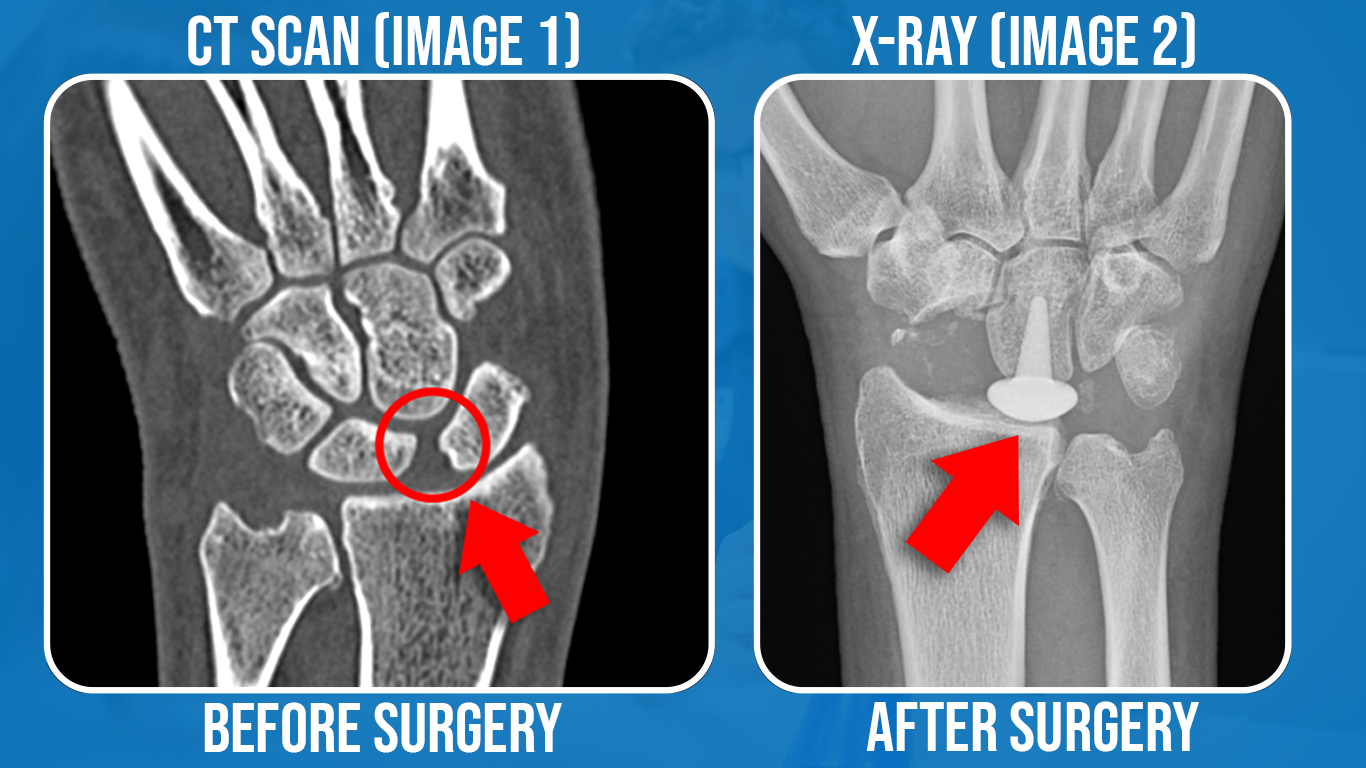

Sometimes a seemingly minor injury can have severe long-term consequences. This fit, active gentleman in his 30s was doing a boxing fitness class about 3 years ago when he mis-hit a punching bag. He initially shrugged off his wrist pain as a simple sprain, but when it failed to improve he eventually had an MRI which showed a rupture of his scapholunate ligament. This is a tiny ligament, but a very important one for providing stability between the small carpal bones in the wrist. Surgical repair was attempted, but it ruptured again. His CT scan (Image 1) shows a wide gap between the scaphoid and lunate bones - a very characteristic sign of widespread instability through the wrist region.

Even severe damage or instability sometimes results in very little pain, but unfortunately for this gentleman, he had significant, constant wrist pain which was affecting his work and his daily life. A few weeks ago he underwent a rather dramatic operation called a 'Proximal Row Carpectomy'. As shown in his post-op X-ray (Image 2) the surgeon completely removed his Scaphoid, Lunate and Triquetrum - the 3 carpal bones nearest to the radius and ulna in the wrist joint. A pyrocarbon implant - looking like a giant thumb-tack on the X-ray - was used to provide a pivot point for wrist joint movement.